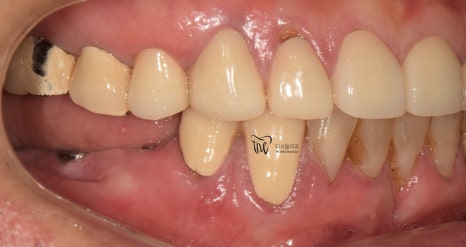

이 분이 저희 치과에 처음 오셨을 때는,

구강 내 여러가지 문제점들을 안고 오셨었습니다.

1.치경부마모증

2.어금니 결손

3.치아 통증

등의 문제들이 많으셨었죠.